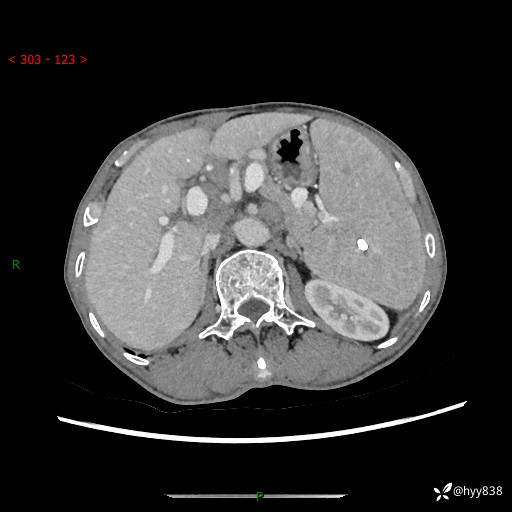

老年男性,脾大并脾脏弥漫粟粒状低密度,淋巴瘤 VS 肉芽肿 VS 血管瘤---结果公布

简要病史: 患者于3月前无明显诱因出现脾大,伴腹部轻微不适,具体不详,无腹痛、腹泻、腹胀,无头晕、头痛、乏力,无恶心、呕吐、呕血,无胸闷、气短、胸痛不适

上腹部CT平扫+增强